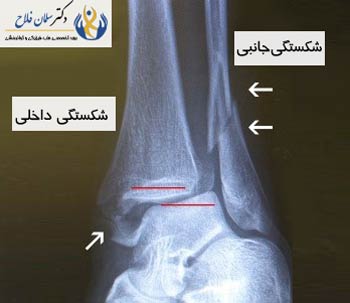

درصورتیکه شکستگی ناپایدار مچپا رخ دهد آسیب وارده باعث درهم شکستهشدن ساختارهای داخلی (سمتداخل) مچپا میشود. این نوع آسیب باعث لق شدن بخش پایینی مچپا میشود (استخوان قوزک) و موقعیت آن کمی به داخل مفصل قوزک کشیده میشود. این ساختارهای چند تکه شده یا شامل قوزک داخلی (برآمدگی استخوان مچپا) و یا رباط دلتوئید (رباط نیرومندی که از بخش داخلی مفصل قوزک حفاظت میکند) میشوند.

پس از جراحت قوزکپا، نکته حائز اهمیت معاینه ناحیه آسیبدیده توسط یک پزشک متخصص جهت تشخیص و درمان صحیح است. اگر قادر نیستید این کار را سریع انجام دهید، به اتاق اورژانس بروید و هرچه سریعتر مراحل معاینه کامل را نزد پزشک متخصص تکمیل کنید. جراح متخصص پا و قوزکپا با لمس کردن نواحی آسیبدیده به معاینه آن میپردازد. علاوه براین ممکن است جراح در صورت ضرورت از بیمار درخواست عکسبرداری اشعه ایکس و سایر معاینات میکند.